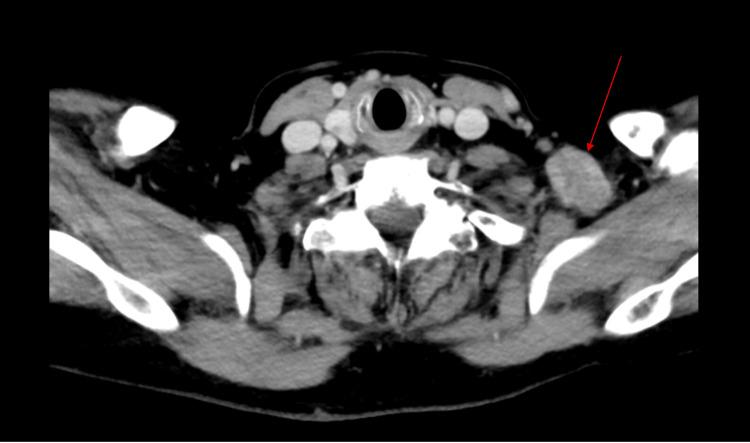

Breast cancer recurrence can occur many years after the initial treatment, particularly in hormone receptor-positive (HR+) cases, where the risk of late recurrence remains significant. Late recurrences are well documented, with research showing that they can happen even decades after the primary diagnosis, necessitating extended monitoring and personalized therapeutic approaches. A 65-year-old woman with a history of stage IIIC invasive ductal carcinoma, initially treated with neoadjuvant chemotherapy, bilateral mastectomies, adjuvant chemoradiation, and prolonged hormonal therapy, presented 10 years later with metastasis to the left supraclavicular lymph nodes. A biopsy confirmed recurrent ER+/PR+/HER2- (estrogen receptor-positive/progesterone receptor-positive/human epidermal growth factor receptor 2-negative) breast cancer. Her treatment was adjusted to include Faslodex (fulvestrant) and Verzenio (abemaciclib), followed by the surgical resection of the metastatic lymph node. Managing HR+ breast cancer involves significant challenges, mainly due to the potential for late recurrence. Even after aggressive treatment and years of remission, dormant tumor cells may become active again, leading to metastasis in less common sites, like the supraclavicular lymph nodes. This situation demands a tailored therapeutic approach, adjusting treatment strategies to address the specific characteristics of the recurrent tumor. In conclusion, late recurrence in HR+ breast cancer requires vigilant long-term follow-up and personalized treatments to effectively manage recurrence risk. Understanding dormancy and reactivation mechanisms is essential for guiding clinical decisions. Prioritizing individualized follow-up strategies and refining treatment protocols will be key to improving patient outcomes and maintaining quality of life.

乳腺癌复发可能在初始治疗多年后发生,尤其是在激素受体阳性(HR+)的病例中,晚期复发风险仍然很高。晚期复发有充分的文献记载,研究表明,它们甚至可能在初次诊断数十年后发生,因此需要延长监测时间并采取个性化治疗方法。一名65岁女性,有IIIC期浸润性导管癌病史,最初接受了新辅助化疗、双侧乳房切除术、辅助放化疗和长期激素治疗,10年后出现左锁骨上淋巴结转移。活检证实为复发性ER+/PR+/HER2-(雌激素受体阳性/孕激素受体阳性/人表皮生长因子受体2阴性)乳腺癌。她的治疗方案调整为包括芙仕得(氟维司群)和唯择(阿贝西利),随后对转移性淋巴结进行手术切除。管理HR+乳腺癌面临重大挑战,主要是因为存在晚期复发的可能性。即使经过积极治疗和多年缓解,休眠的肿瘤细胞可能会再次活跃,导致在不太常见的部位发生转移,如锁骨上淋巴结。这种情况需要量身定制的治疗方法,调整治疗策略以应对复发性肿瘤的特定特征。总之,HR+乳腺癌的晚期复发需要长期密切随访和个性化治疗,以有效管理复发风险。了解休眠和重新激活机制对于指导临床决策至关重要。优先考虑个体化随访策略并完善治疗方案将是改善患者预后和维持生活质量的关键。